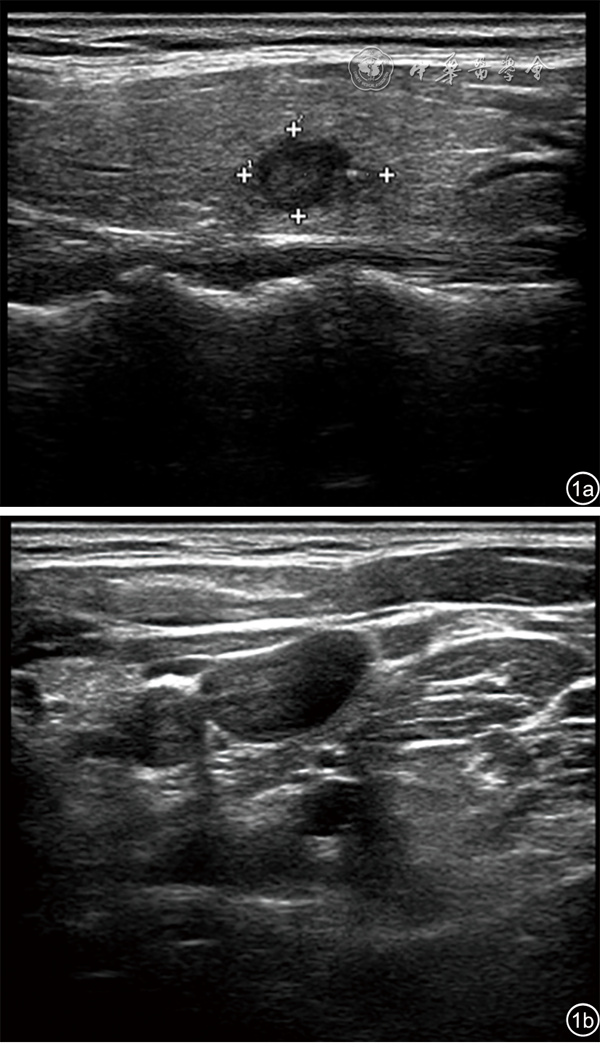

图1 55岁男性患者甲状腺左叶11.5 mm×7.0 mm低回声结节,超声表现为结节横径<20 mm(图a),结节纵径<10 mm(图b)。病理诊断为甲状腺乳头状癌(左侧),颈侧区淋巴结未见转移(左侧)